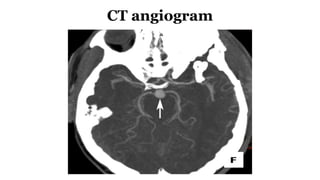

CT angiogram